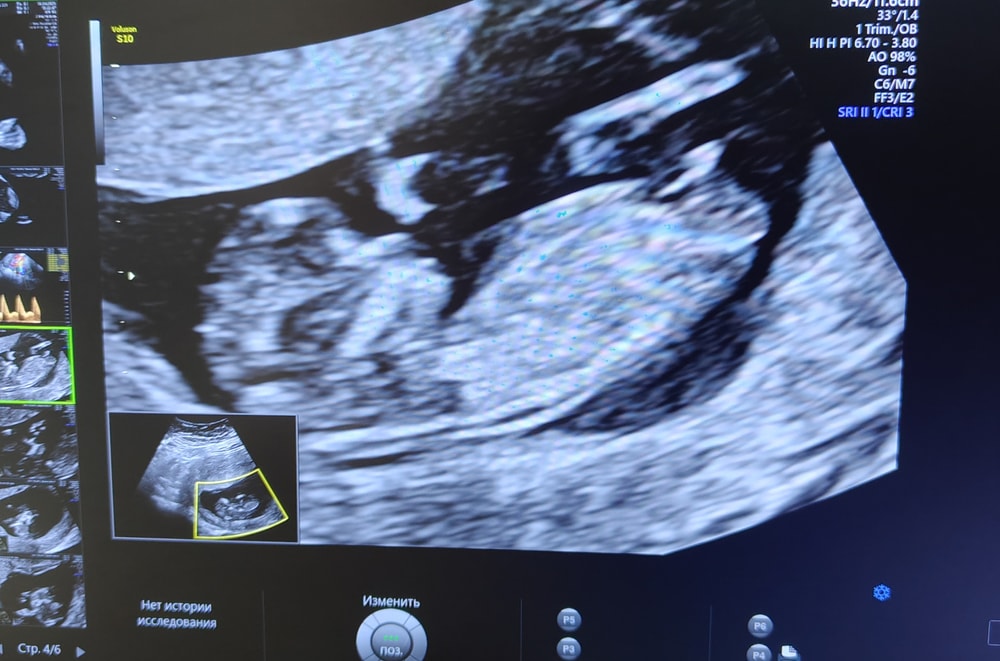

Ксения , понятно что главное здровый , но ох как я надеюсь что сегодняшняя девочка на узи не станет мальчиком на втором скрининге 🤣🌺🙏🙏 после двух мальчиков мне девочки кажутся чем то инопланетным и недосягаемым 🤣 хотя да, соглашусь, сыновья зачаты точно в овуляцию

Пуповина между ног Срок по узи 15 недель и 5 дней. Пол ребёнка?